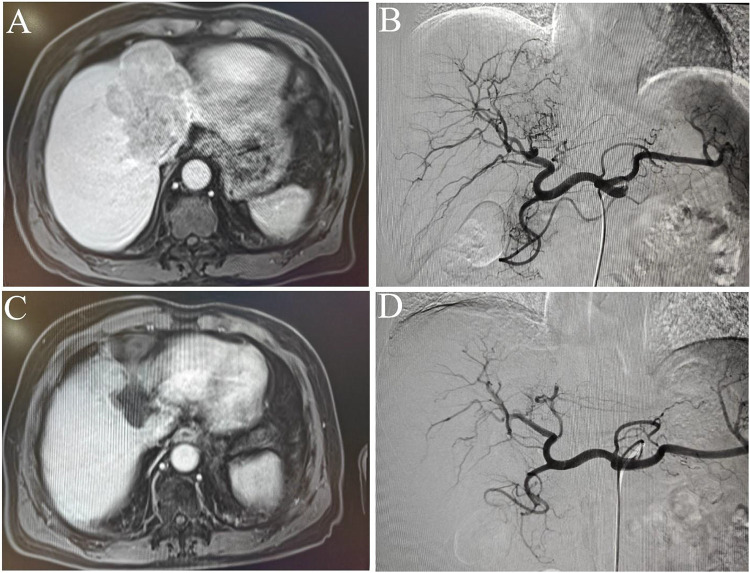

背景:本研究旨在评估肝动脉灌注化疗(HAIC)联合阿帕替尼和camrelizumab治疗肝切除术后复发性肝癌(HCC)患者的疗效和安全性。方法:回顾性分析2020年7月至2024年12月连续接受HAIC联合阿帕替尼/卡莫来珠单抗治疗的复发性HCC患者的病历。评估主要结局,包括总生存期(OS)、无进展生存期(PFS)、治疗反应和治疗相关并发症。结果:研究随访至2025年1月31日,中位随访时间11个月(范围:2-26个月)。在110例符合条件的HCC复发患者(91例男性,19例女性)中,有62例死亡。客观有效率(ORR)为31.8%,疾病控制率(DCR)为87.3%。中位生存期为14个月(95% CI: 12.9-15.1个月),多变量分析确定血管侵犯是生存期的独立预后因素。中位PFS为7个月(95% CI: 5.3-8.7个月),血小板与淋巴细胞比率是PFS的独立预后因素。所有不良事件均在可控范围内,未发生与治疗相关的死亡。结论:HAIC联合阿帕替尼/camrelizumab治疗肝切除术后复发性HCC有效、安全,可能是一种有前景的治疗复发性HCC的方法。